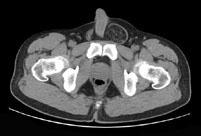

男,29岁,因左腹股沟突发痛性肿物3小时入院,左腹股沟皮下环处有一约4cm×5cm的肿物,触痛甚,质软,基底部有一细蒂,左阴囊发育小,睾丸缺如,CT检查如...

问题 男,29岁,因左腹股沟突发痛性肿物3小时入院,左腹股沟皮下环处有一约4cm×5cm的肿物,触痛甚,质软,基底部有一细蒂,左阴囊发育小,睾丸缺如,CT检查如图所示,下列说法错误的是 ( )

选项 A、腹股沟斜疝 B、左腹股沟区肿块为曲张的精索静脉 C、精索静脉曲张 D、腹股沟直疝 E、左睾丸下降不全

答案 D